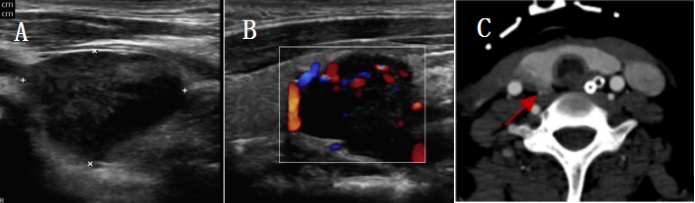

1.3.2 影像学检查2021-04-14彩色多普勒超声:右侧甲状腺下极下方低回声,大小2.3 cm×1.5 cm,边界清,甲状旁腺来源首先考虑(图 1A, B);双肾B超提示:双肾肿大伴肾病表现。2021-04-17颈部CT:右侧甲状腺后方结节(图 1C)。心脏超声:主瓣瓣环及二尖瓣瓣环及二尖瓣腱索上多发钙化,左室壁偏厚,肺动脉压增高。肺部CT:两肺炎症病变,两侧少量胸腔积液(图 2A)。

| A, a患者甲状旁腺腺瘤切除术前2021-04-13肺部CT;B, b患者术后第3天2021-04-25肺部CT;C, c患者术后第10天2021-05-02肺部CT;D, d患者术后第25天2021-05-17肺部CT 图 2 转移性肺钙化治疗前后的胸部CT影像 |

2021-04-22患者在全麻下行右侧甲状旁腺腺瘤腔镜下切除术,术后病理报告:(右侧)符合甲状旁腺腺瘤。术后血清总钙2.45 mmol/L,甲状旁腺激素27.7 pg/mL, 停鲑降钙素肌肉注射治疗。CRRT设定血流量与枸橼酸钠泵速比为1∶1.3,监测血气分析调整静脉端补钙剂量,维持离子钙1.0~1.2 mmol/L范围,患者术后第2天经呼吸锻炼后脱机成功,气管切开处高流量吸氧。2021-04-25停止CRRT治疗。肺部CT:两肺炎症病变,较前吸收(图 2B, b)。2021-04-28停用抗生素治疗,改为鼻导管吸氧,开始床边坐起进行关节功能锻炼。2021-05-02肺部CT:两肺渗出性病变,较前明显吸收(图 2C, c),2021-05-09患者转康复病房进行肺功能训练、平衡功能训练、关节功能锻炼、中药辅助治疗。2021-05-17复查肺部CT:两肺渗出性病变,较上次明显吸收(图 2D, d)。2021-05-26血气分析:PH 7.37, 乳酸0.60 mmol/L,二氧化碳分压31.70 mmHg, 氧分压117.00 mmHg(1 mmHg=0.133 kPa), 氧饱和度100%(吸入氧流量21%),标准碳酸氢盐19.2 mmol/L。肾功能:肌酐104 μmol/L,肾小球滤过率61 mL/min,血清钙1.93 mmol/L。双上肢肌力5-级,双下肢肌力4+级,坐位平衡3级,立位平衡2级,2021-05-28患者要求出院回当地继续康复治疗。

pHPT伴MPC快速进展案例较为罕见,研究[5]表明原发性HPT伴高钙血症、原发性HPT、高钙血症和继发性HPT伴肾功能衰竭、维生素D缺乏症、骨髓瘤等疾病是MPC的危险因素,能否有效控制高钙血症和高PTH是治疗的关键。本例患者采用含钙1.50 mmol/L的置换液进行RCA-CRRT联合鲑降钙素降钙治疗,为进一步诊断及手术治疗赢得了时间,患者在切除右侧甲状旁腺腺瘤病灶后,肺钙化症状明显改善(图 2D, d),表明pHPT伴MPC手术治疗后有逆转的可能。